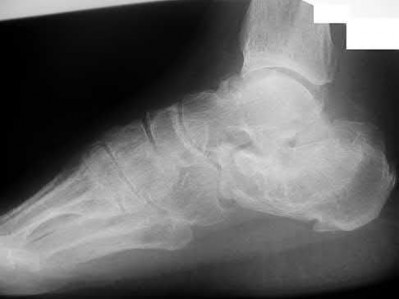

Figure A shows a patient after an open reduction and internal fixation of a bimalleolar ankle fracture.

Egol et al showed that by nine weeks, the total braking time of patients who had undergone fixation of a displaced right ankle fracture returns to the normal, baseline value.

Egol et al, also found that appropriate braking time returns at a point 6 weeks after initiation of weightbearing after treatment of lower extremity long bone and periarticular fractures, as examined with a driving simulator. No differences were seen in return of braking time between periarticular fractures and long bone injuries.